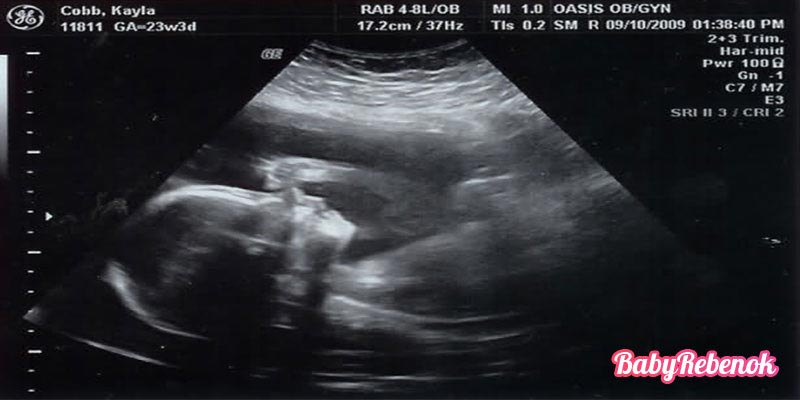

Фото УЗИ на 23 неделе беременности

На 23 неделе беременности врачом может быть назначено проведение ультразвукового исследования плода. Нельзя его игнорировать так же, как и плановые осмотры у гинеколога. Процесс является безопасным как для мамы, так и для плода, и позволяет вовремя диагностировать осложнения беременности и аномалии развития малыша. На УЗИ оцениваются следующие показатели:

- развитие плода;

- размеры, соответствующие сроку беременности;

- двигательная активность;

- количество сердцебиений;

- пол малыша;

- размер и состояние матки;

- расположение плаценты.